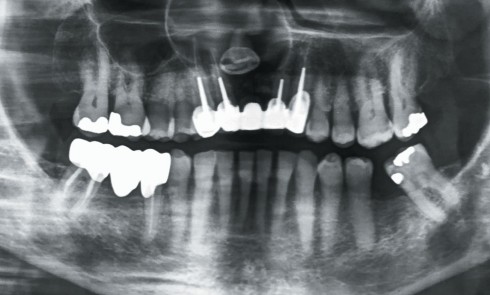

Article réservé à nos abonnés À propos d’une lésion maxillaire

1. La panoramique (fig. 1) montre « une image » maxillaire antérieure. Il s’agit : a. d’une image radioclaire maxillaire b. d’une image radio-opaque...